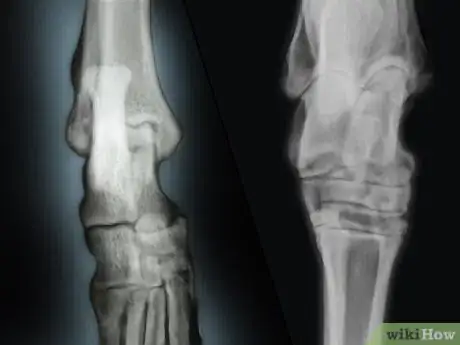

2Let the vet take an X-ray of your dog’s affected leg. The vet may then sedate or anesthetize your Rottweiler so she can take X-rays of your dog’s hock and any other areas that may be sore. Usually, two views are taken of your dog’s hock in the X-rays. One view is taken from front to back (anterior-posterior) and one view is taken side to side (lateral).[6]

- Doing two views in the x-rays will help the vet rule out other conditions such as a fracture, an infection, and cancer. However, X-rays are not a foolproof way to detect OCD in your dog’s hock. In the early stages of the condition, the only clear evidence of OCD is a flap of cartilage on your dog’s hock or a chip off the cartilage. It may be difficult to spot these small issues on an X-ray.